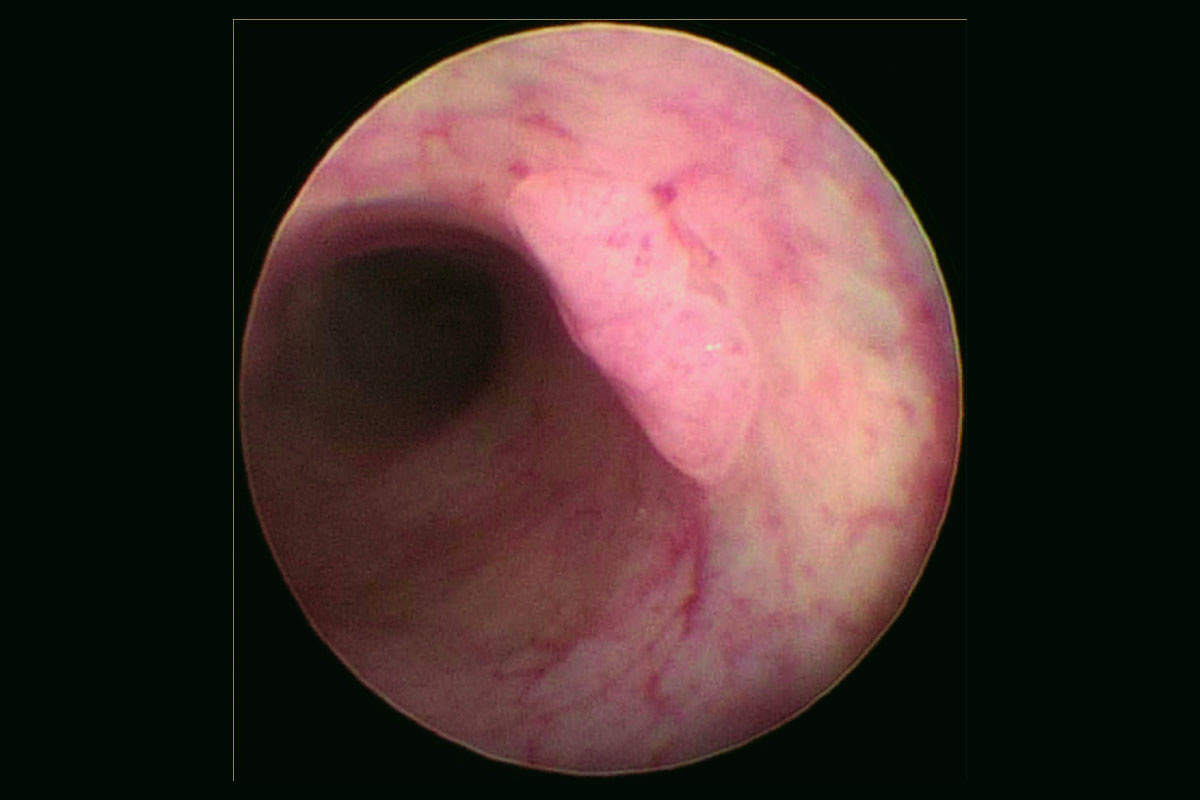

The endoscopic view of the patient-derived tumoroids implanted in the NOD-SCID (NSG) mouse distal rectum.